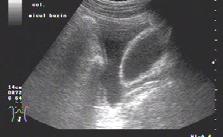

• contractilitatea globală a ventriculului stâng, identificând mărimea și statusul contractil – prezența unei insuficiențe cardiace acute (fig.2) cu necesitatea administrării medicației diuretice, inotrope, vasoactive în funcție de parametrii hemodinamici și corelarea cu aspectul plămânului și a venei cave; vizualizarea unui ventricul stâng hiperkinetic, cu reducerea volumui cavității (fig.3) ceea ce indică corelat cu aspectul VCI cu diametru redus (fig.4) o stare de hipovolemie ce necesită administrarea de fluide;

Fig.2. Secțiune subxifoidiană. Cord dilatat. Perete ventricul stâng redus în dimensiuni

Fig.3. Secțiune subxifoidiană. Cord hiperkinetic (cavități reduse)